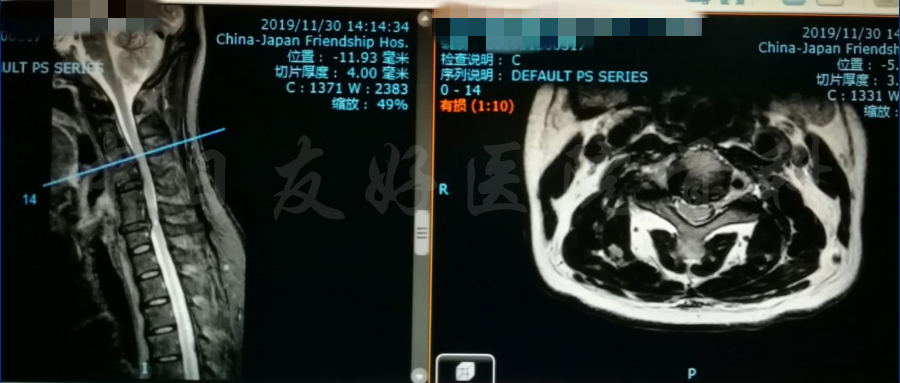

MRI

MRI颈4-5(左)、颈5-6(中)颈6-7(右)

矢状位MRI

轴位MRI:腰3-4(左)、腰4-5(中)、腰5骶1(右)

颈椎MRI

颈椎MRI

颈椎各节段MRI(上下滑动)

腰椎MRI